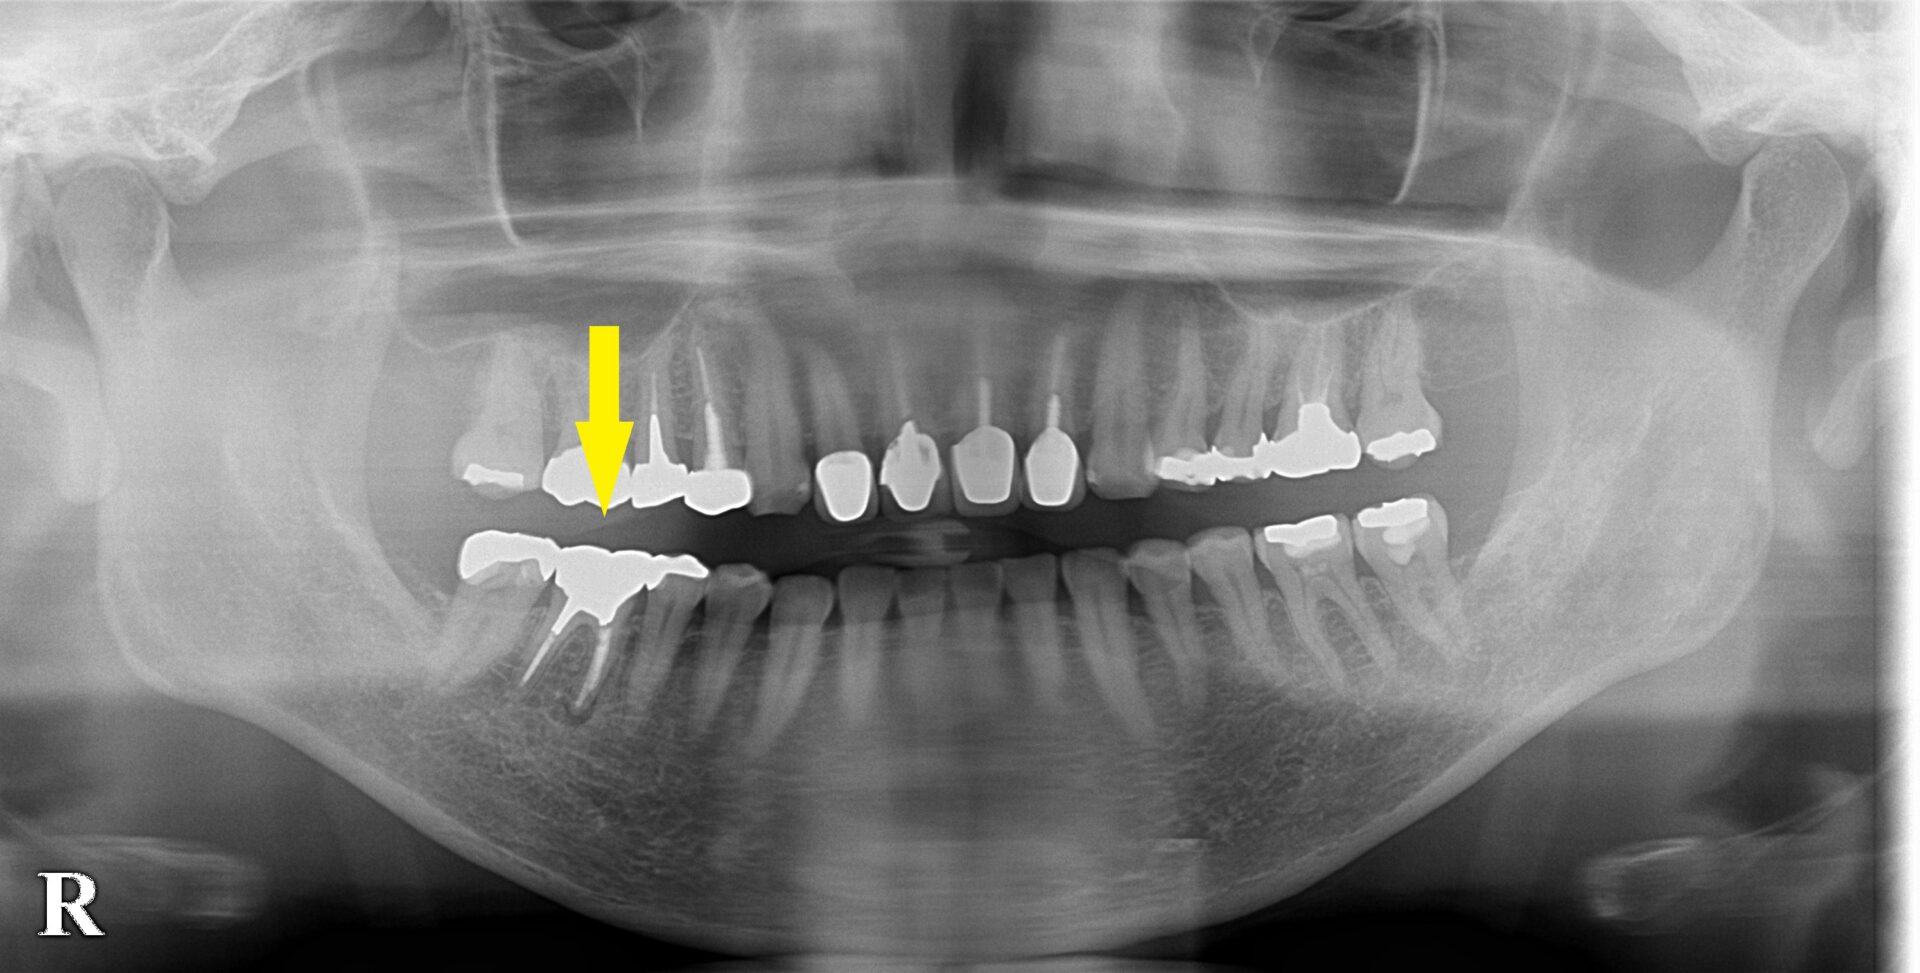

下顎第一大臼歯の骨造成症例

右下顎第一大臼歯が以前から腫脹を繰り返し、何度か歯根の治療を受けられたのですが改善しなかったそうです。

今回、根管治療専門の歯科医院を受診されて、検査、診察を受けられたところ、治療しても治る可能性は低いと言われたそうです。

もうひとつの歯科医院では、抜歯してインプラントを勧められたそうで、その後、どうしたら良いかと、当院に相談においでになりました。

根の治療は十分されていて、この結果ですので、あきらめがつくようなら、抜歯、インプラントをお勧めしました。

CTで見ると、頬側の骨が吸収されてしまっているので(下の2段目左)、抜歯して、治癒を待ってからインプラントの埋入を行うこととしました。